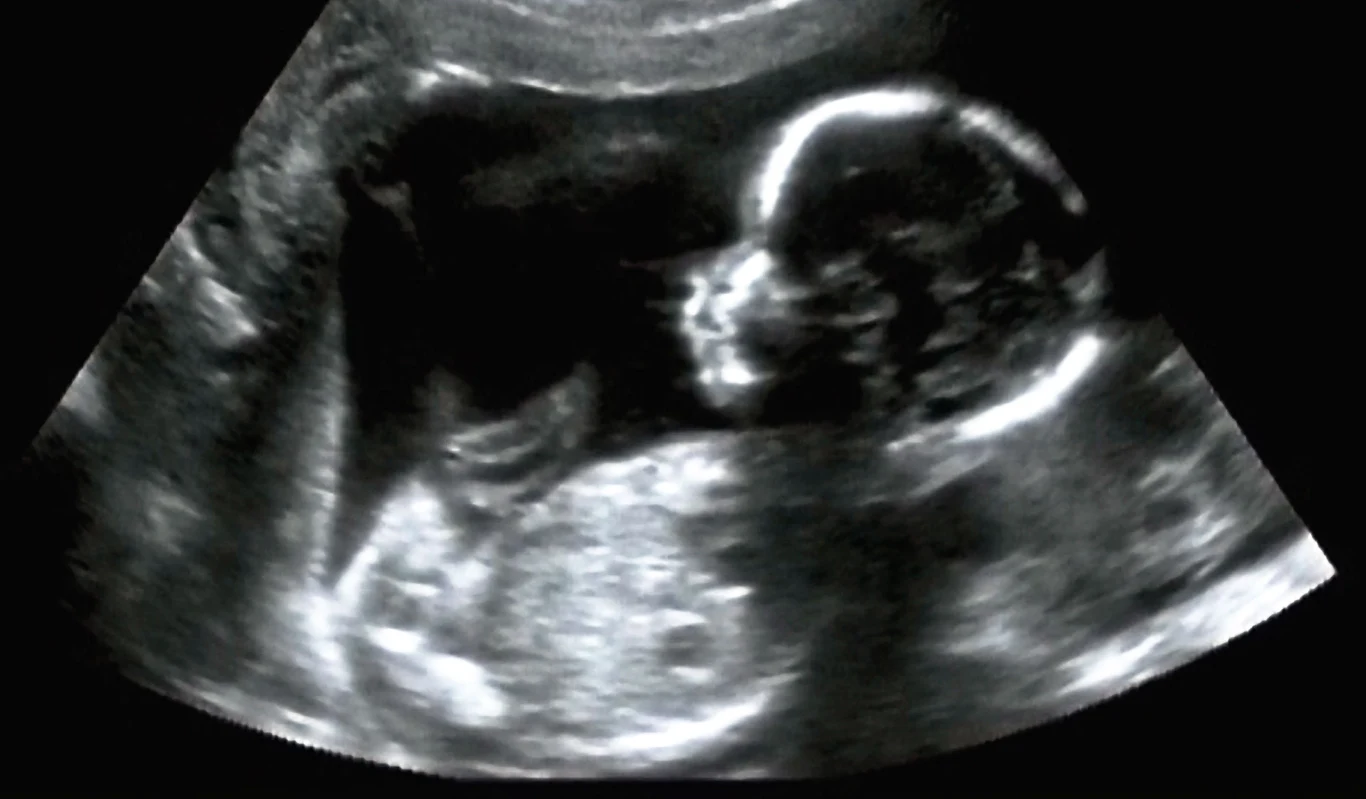

Biobag, bo tak nazywane jest to rozwiązanie, odwzorowuje naturalne środowisko płynu owodniowego otaczającego płód w łonie matki, a niezbędne elementy, takie jak ciągły dopływ tlenu, są dostarczane bezpośrednio do krwiobiegu płodu za pośrednictwem specjalistycznego urządzenia podłączonego do pępowiny.

Wyniki testów na zwierzętach pokazują, że owcze płody rozwijały się i dobrze prosperowały w worku Biobag przez okres do czterech tygodni po przeniesieniu z naturalnej macicy - mowa o etapie rozwojowym podobnym do ludzkiego odpowiednika 23-24 tygodnia ciąży.